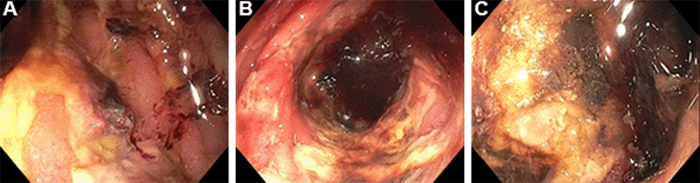

Four months after 90Y TARE, the patient presented to the emergency department with abdominal pain, CT exhibiting a perihepatic fluid collection, and possible small bowel obstruction versus ileus. She was admitted for nonoperative management and small bowel follow-through confirmed ileus. Endoscopy during this admission demonstrated resolution of the previously visualized jejunal ulcers bordering the DJ anastomosis but identified two new, deep, 1 cm ulcers just distal to the HJ anastomosis (Figures 3A and 3B). Biopsy noted enteritis but no evidence of malignancy, ischemia, or presence of 90Y microspheres. Serum gastrin and chromogranin A levels from the month prior were both normal. She was managed conservatively and discharged on twice-daily PPI and sucralfate.

The patient continued to experience severe, stabbing abdominal pain, and follow-up endoscopy one month later revealed increased size of the jejunal ulcers adjacent to the HJ anastomosis (Figure 3C). She was admitted to the hospital, and a CT scan was obtained, with findings suggestive of erosion between the liver and an adjoining segment of the jejunum. On exploratory laparotomy, after extensive lysis of adhesions, a 1 cm jejunal segment distal to the HJ anastomosis was adherent to the liver with a contained jejunal perforation and fistulous tract into the radiated segment V lesion. The HJ and DJ anastomoses were noted to be intact, and the remainder of the visible jejunal mucosa appeared healthy. The jejunal perforation and 1 cm of bowel on either side were resected, and an end-to-end jejunojejunostomy was matured. Surgical pathology showed small bowel mucosa with erosion, ulceration, fistula formation, edema, and serosal adhesions but was negative for neoplasm or evidence of 90Y microspheres  (Figure 4).

Figure 3. Endoscopy Demonstrating Healthy Jejunal Mucosa. Published with Permission

A) Duodenojejunostomy anastomosis; B) two new ulcers adjacent to hepaticojejunostomy anastomosis (yellow arrowheads); and C) increased size of ulcers on follow-up endoscopy.